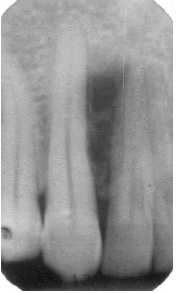

What is a radicular cyst?

What’s the difference between a chronic and an acutely developed cyst?

See image